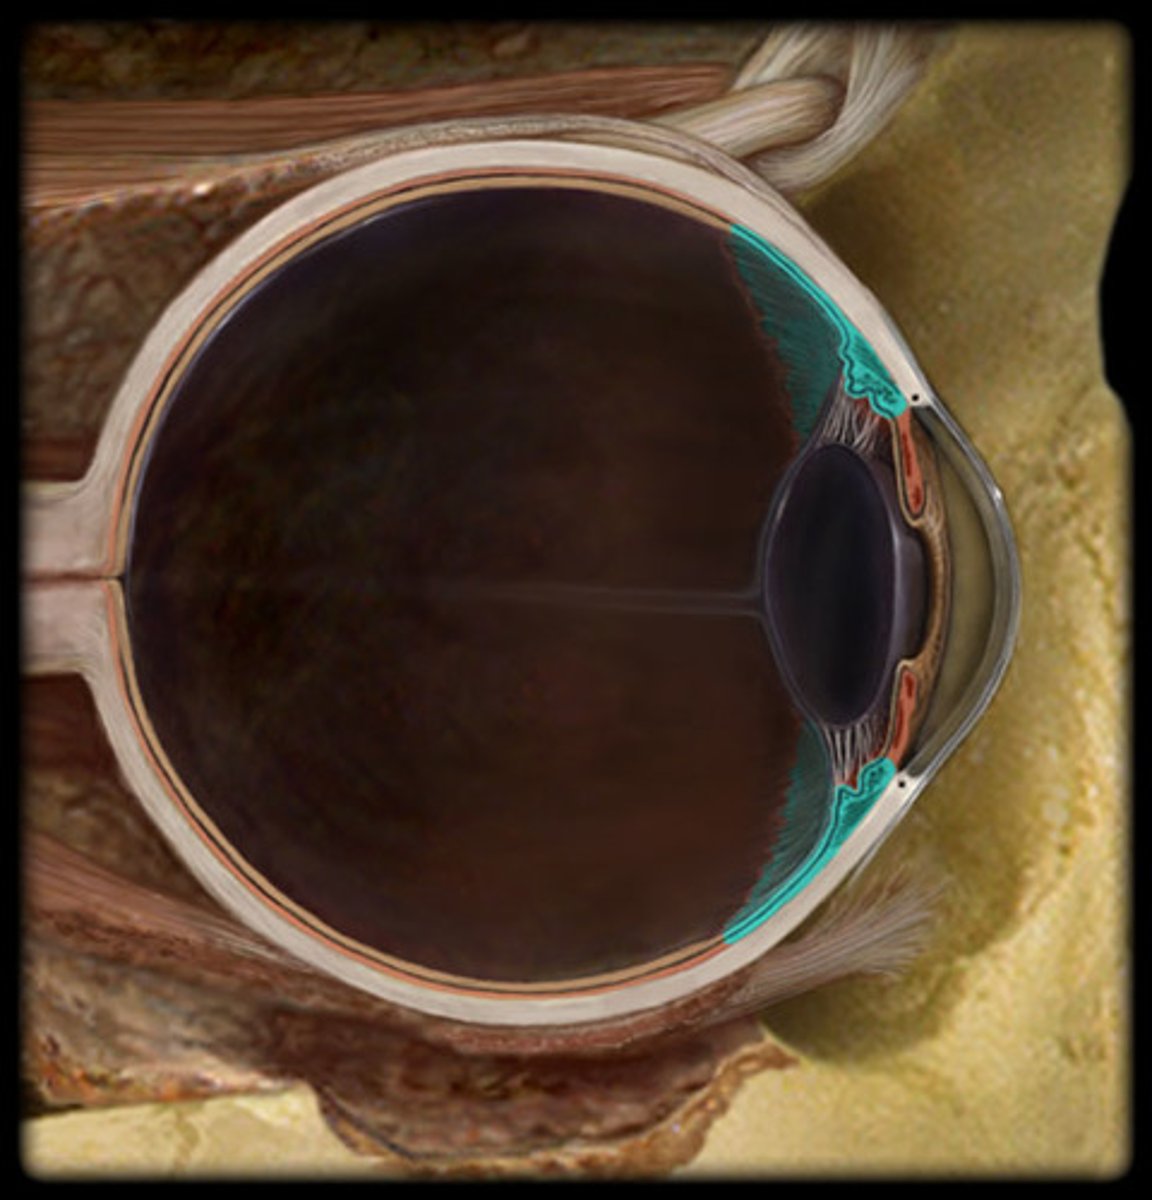

choroid

ciliary body

Retina

Iris